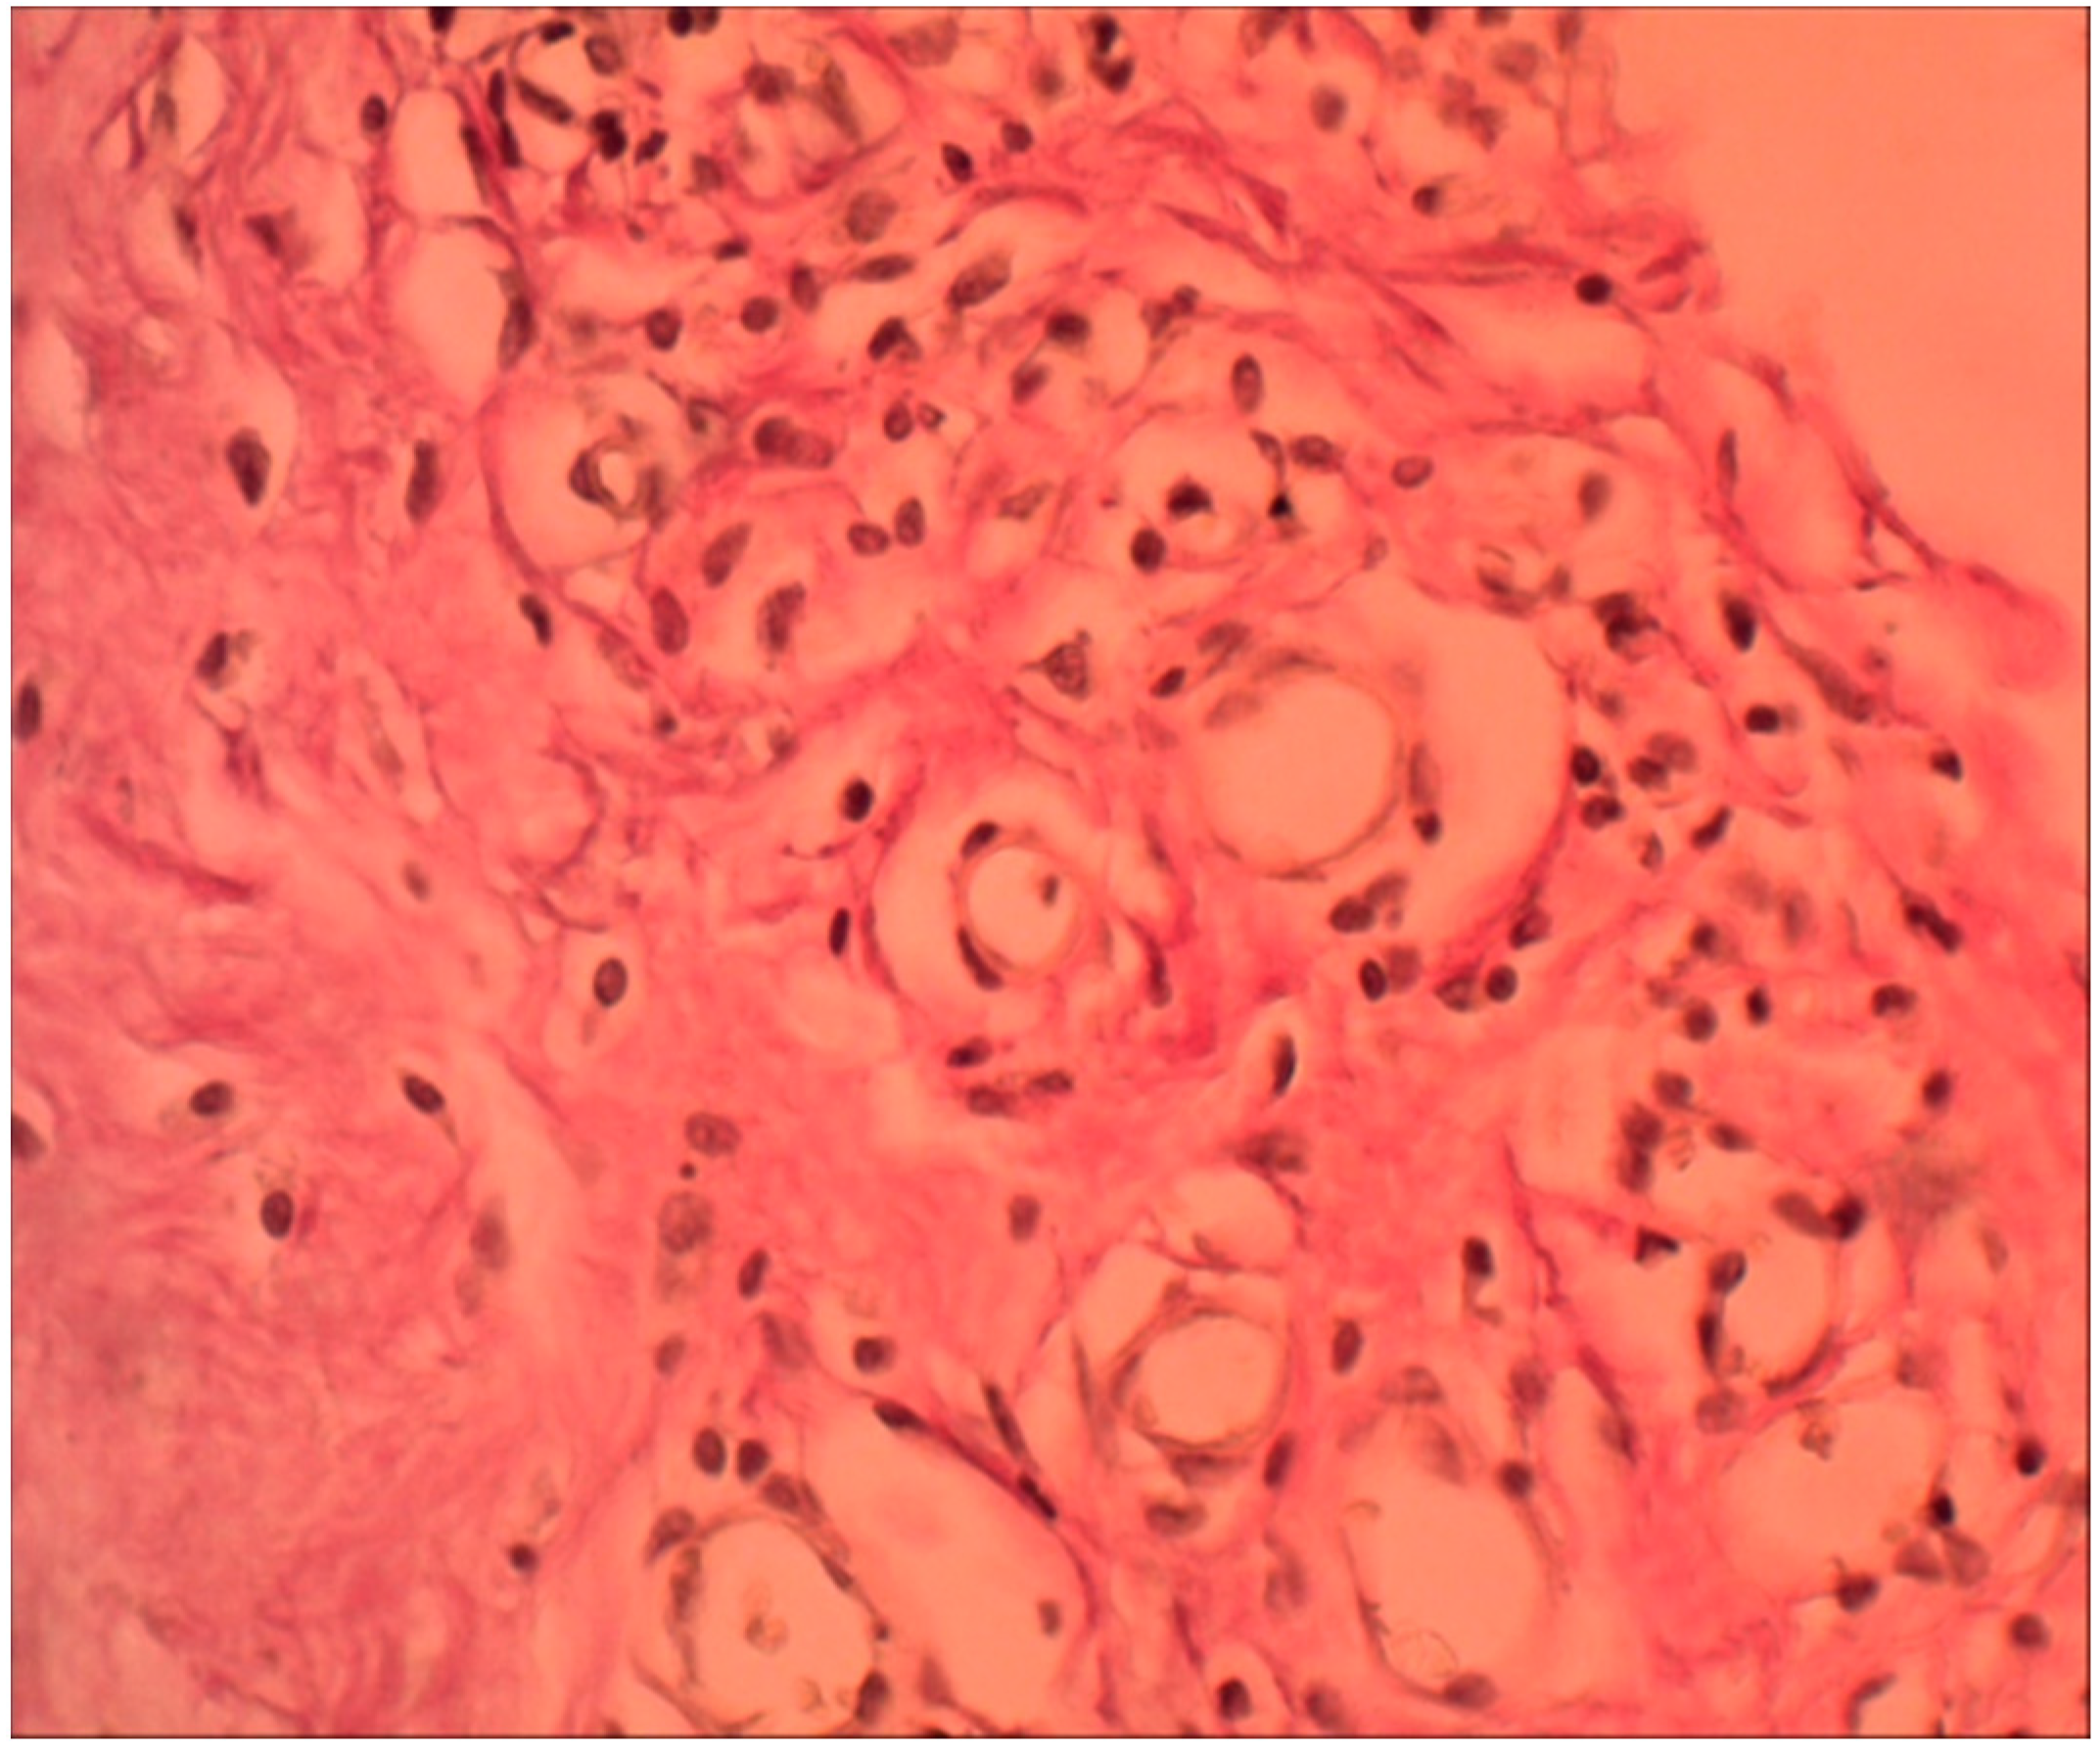

- The result of the fibroblastic reaction was the development of dense irregular connective tissue at a distance from the border with the biopolymer after the acute phase of inflammation.

- In vitro, the polymer biodegradation began from week 2. According to the spectrometry data, this process was not linear; in the first two months, the Mw and Mn values remained virtually unchanged from week 2. At three months, the Mw value was 14.4% less than the initial value. The degradation process in tissues, according to the spectrometry data during three months of implantation, remained unclear in the course of this research. The Mw and Mn values for the biopolymer from tissues after three months of implantation were greater than these values for the polymer degrading in vitro at three months and even at 0 months. Complex metabolic processes in tissues during inflammation and involving various chemical agents can explain this contradiction. The data obtained can serve as a basis for further, more detailed study of the physical parameters of polymer degradation in tissues and in vitro. However, the in vitro results confirm a delayed degradation period of at least a month, which was confirmed by the histological study of peri-implantation tissues. According to histological studies, cell migration into the biopolymer began in the first month of the experiment. This is somewhat earlier than the polymer degradation processes in vitro. As described above, during this period, macrophages were predominantly in direct contact with the biopolymer. Based on this, it can be assumed that macrophages are active participants in the biotransformation process and absorb polymer chains of the biopolymer as a result of phagocytosis. This assumption can also serve as a subject for future studies to determine the molecular weight of polymer chains formed during degradation and the ability of macrophages to absorb these chains, determining the rate of biopolymer biotransformation.